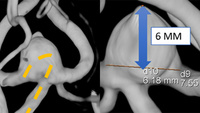

Microcatheter control in the management of a wide-neck Acom aneurysm

The Microchap™ microcatheter ease navigability and provides stability during intracranial procedures. Its design can be useful for accessing or securing recurrent branches located at the aneurysm neck. By enabling rapid catheterization, it may help reduce the risk of vessel injury or aneurysm perforation. This innovation may contribute to improving the endovascular management of complex intracranial aneurysms.​ [...]